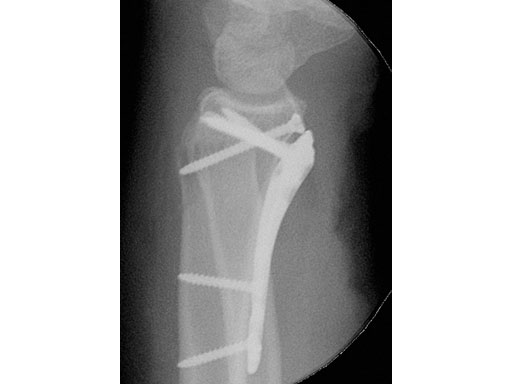

A young woman, 1,5 m tall, 45 kg, sustained a very distal C1.1 fracture of the distal radius.

Fig 2 Stabilization of the radiocarpal articular surface with one single 2.4 mm screw at the level of the watershed line, and narrow plate below the watershed line.